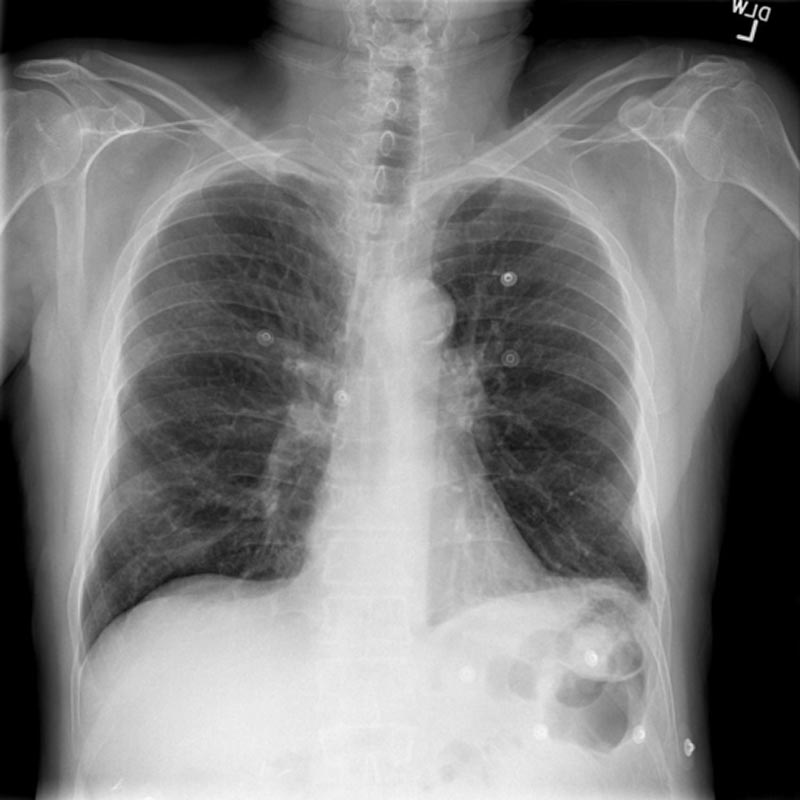

COPD CXR - hyperinflated only.jpg

This is a 55-year-old female with a history of CHF and COPD who presents with cough and shortness of breath for 3 days. She is found to have a COPD exacerbation. Her bedside ultrasound shows normal cardiac function and no pulmonary edema, so she is treated with nebs and steroids. Learners should be able to distinguish between a CHF exacerbation and COPD exacerbation using ultrasound and manage the COPD exacerbation effectively.